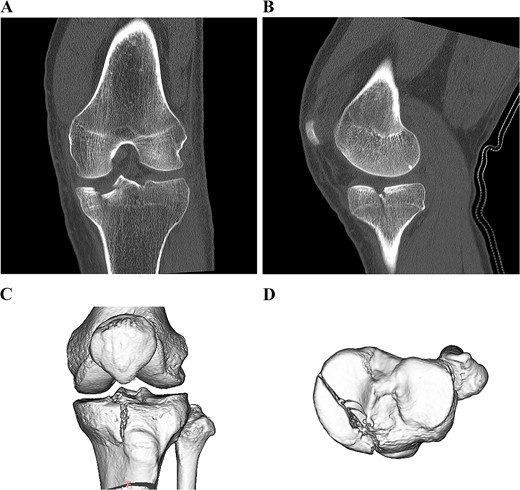

A 49-year-old male patient fell while playing soccer and visited our hospital with severe pain and swelling in his left knee. A lateral-view plain radiograph showed articular depression of the tibial plateau (Fig. 1). Three-dimensional reconstructed computed tomography (CT) scan revealed a 5-mm depression of the medial articular surface and a split in the medial plateau (Fig. 2). The fracture was classified as AO/OTA 41B3.2 and Schatzker type 2 [6, 7]. MRI scan showed a medial femoral cartilage injury that appeared as a kissing lesion opposite the tibial fracture. The length and width of the cartilage defect on the femoral condyle were 18 mm and 20 mm, respectively (Fig. 3). A part of the peripheral cartilage around the defect was suspected to be delaminated, and the defect was estimated to exceed 4 cm2.

Preoperative CT scan images of the left knee. Coronal and sagittal CT scan images (A, B). 3D CT scan images (C, D).

A 5-mm depression in the medial articular surface and column fracture of the tibial plateau are revealed.